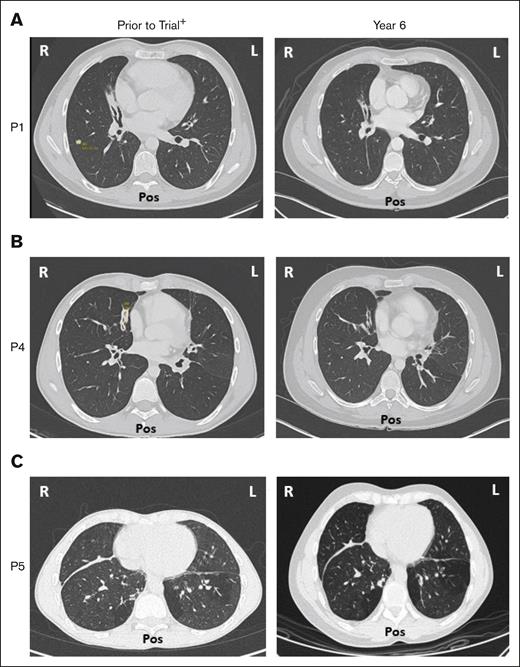

Five of 6 patients had a history of respiratory disorders. Half had bronchiectasis before receiving leniolisib; none progressed and all are stable at year 6 (Figure 7). Pulmonary function tests in 5 of 6 patients revealed no new or worsening conditions through year 6.

Bronchiectasis throughout treatment with leniolisib. Lung computed tomography scans from (A) P1, (B) P4, and (C) P5 who developed bronchiectasis before entry into the trial (left) and year 6 of treatment with leniolisib (right). L, left; Pos, posterior; R, right. +Images for P1 and P4 were taken ∼1 year before entry into the DFT, and the image for P5 was taken ∼4 years before exposure to leniolisib.

Bronchiectasis throughout treatment with leniolisib. Lung computed tomography scans from (A) P1, (B) P4, and (C) P5 who developed bronchiectasis before entry into the trial (left) and year 6 of treatment with leniolisib (right). L, left; Pos, posterior; R, right. +Images for P1 and P4 were taken ∼1 year before entry into the DFT, and the image for P5 was taken ∼4 years before exposure to leniolisib.